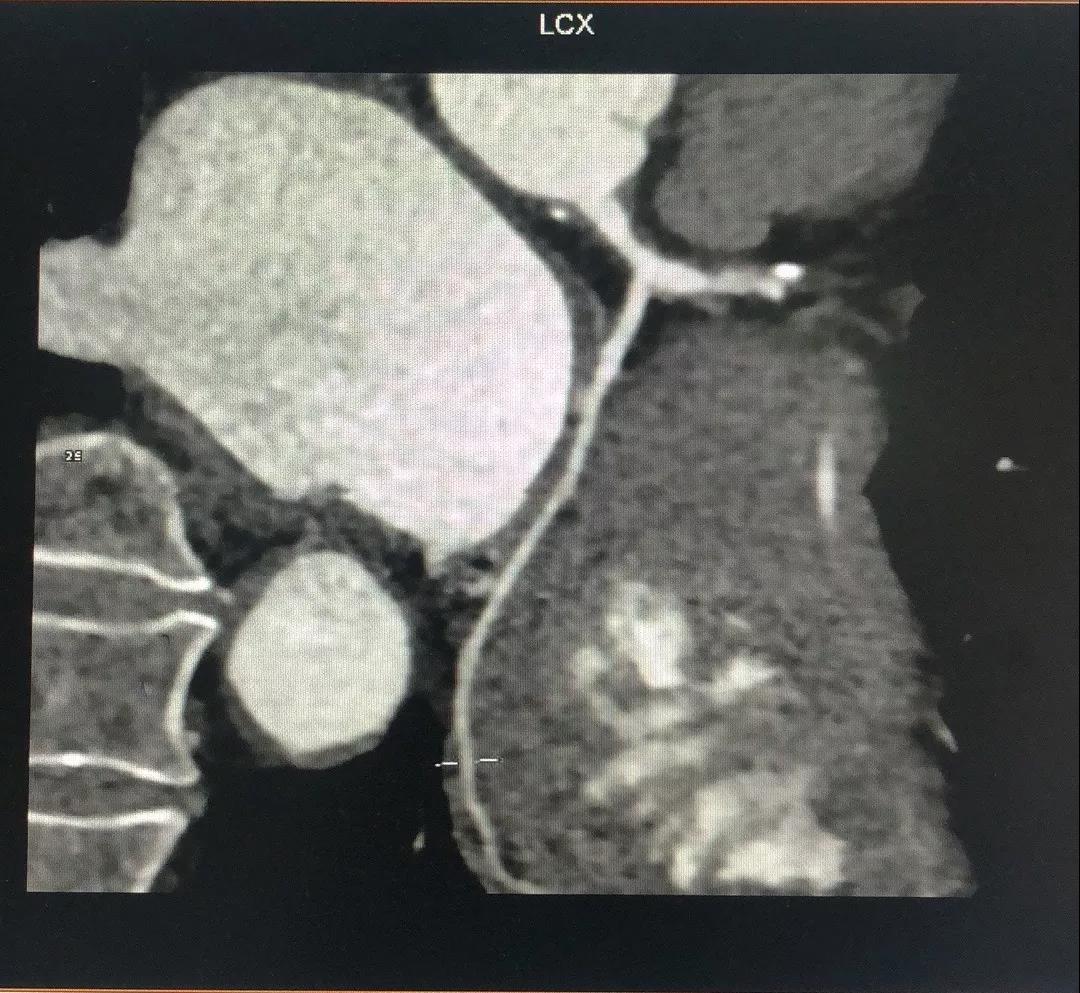

关于RCA

RCA CTA特点

1、入口清楚;

2、闭塞段长度小于20cm;

3、闭塞段血管无明显扭曲;

4、闭塞段内有两处明显的钙化斑块;

5、闭塞出口处血管相对比较“健康”;

6、侧枝血管汇入左室后支;

7、后三叉处的血管相对比较“健康”。

有了上述信息,再结合冠脉造影资料,开通RCA就有了比较清晰的思路:

1、逆向导丝抵达闭塞出口,Fielder系列引导,迅速交换CP或Gaia3导丝逆向进攻;

2、灵活使用Knucle技术;

3、前向CP或Gaia3导丝正向准备;

4、正逆向导丝交汇/无限接近;

5、Re-Cart,Kissing Wire,AGT;

6、IVUS评估和优化支架植入。